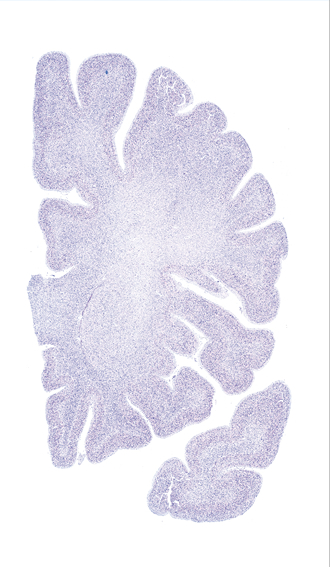

Hi-Resolution Sections · Cells (Nissl Staining) · Virtual Microscopy

Frontal sections (Nissl) from the Atlas Brain:

Slice

Single

Microscopy

Slice ID:

r2-0545

Plate NR:

10-11

Position:

-18,5 mm